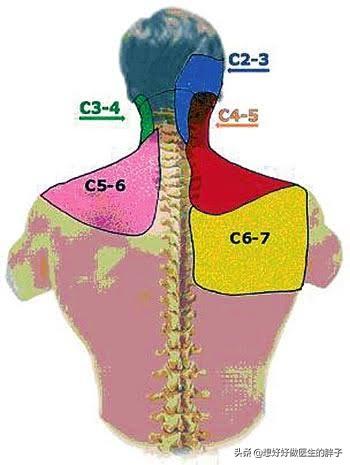

Le nerf dorsal de l'omoplate est innervé par le nerf cervical 5. Par conséquent, si une personne a une mauvaise colonne cervicale, en particulier s'il y a un problème avec l'espace vertébral cervical 4-5 ou une hernie discale dans la colonne vertébrale cervicale 4-5, le nerf cervical 5 sera comprimé, ce qui provoquera une douleur dans la zone du bord médial de l'omoplate.

Le nerf thoracique long est innervé par les nerfs cervicaux 5, 6 et 7. Par conséquent, si la colonne cervicale n'est pas en bon état, notamment en cas d'écart vertébral cervical 5-cervical 6 ou d'écart vertébral cervical 6-cervical 7, ou de hernie discale cervicale 5-cervical 6 et de hernie discale cervicale 6-cervical 7, le nerf cervical 5, le nerf cervical 6 et le nerf cervical 7 seront comprimés, ce qui provoquera une douleur à l'angle inférieur des omoplates, ou le symptôme typique de la douleur de l'avant du thorax contre le dos.

●hernie discale cervicale. Lorsqu'une hernie discale de la colonne cervicale appuie sur les nerfs, elle peut provoquer des douleurs à l'arrière de l'épaule, en particulier au niveau de l'épaule.Compression des racines nerveuses cervicales 6-7Il est possible de ressentir des douleurs autour de l'omoplate.

IV. les nerfs

1, hernie discale, sténose spinale :Lorsque l'oppressionC4, C5, C6.Lorsque la racine du nerf est enfoncée, la douleur se situe au-dessus de l'os de l'épaule. Lorsqu'une pression est exercée sur la racine nerveuse, la douleur se situe au-dessus de l'os de l'épaule.C7, C8.Lorsque la racine nerveuse est enfoncée, la douleur se situe entre les omoplates. Lorsque la pression rencontre laC8La racine nerveuse, la douleur se situe dans les omoplates gauche et droite. La douleur peut être déclenchée en inclinant le cou vers l'arrière et en tournant la tête.。La douleur peut toucher le cou et la tête et le cou, ou irradier vers les doigts.

Les 8 paires de nerfs rachidiens émanant des vertèbres cervicales régulent et innervent la tête et les membres supérieurs, les épaules et les organes et tissus musculaires situés autour du cou, qui comprennent le muscle deltoïde, le muscle supra-épineux et d'autres muscles situés autour de l'épaule. Les 12 paires de nerfs rachidiens émanant de la colonne thoracique innervent et régulent les muscles et autres organes situés autour de l'omoplate. Par conséquent, si les nerfs rachidiens de ces segments de la colonne vertébrale sont comprimés et blessés, il en résultera naturellement une douleur au niveau de l'omoplate, et la plupart de ces douleurs sont principalement des douleurs irradiantes.